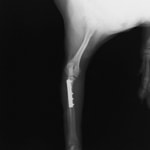

ペルシャ猫 11ヶ月齢 雄

他院にて左大腿骨遠位の成長板骨折(salter-harrisⅠ型)が認められており、治療相談を目的として来院。当院にて、キルシュナーワイヤーを用いたピンニングにより骨折部位の整復を行いました。術後の経過は良好で、現在も経過観察中です。

術後レントゲン

Arthrex社のターゲティングデバイスを用いてピンニングの位置を調整することで、確実な固定を行っています。当院ではこの手術器具以外にも、人の手術にも使用される様々な器具を導入し、手術精度を高め、また医療メーカーと新しい器具の開発、試作にも取り組んでおります。